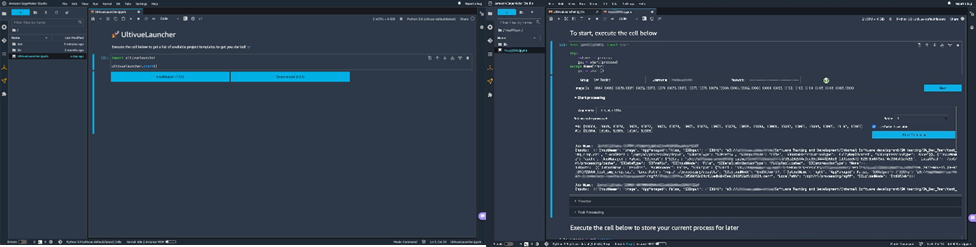

When handling data at the scale that Ultivue does, the need for utilizing the scalability of cloud services is omnipresent. However, the bio-technology space requires medical and biological experts that cannot be experts in software and IT at the same time. Our user interfaces must simplify the use of highly scalable compute services, such as Amazon SageMaker, and at the same time, offer flexibility to a wide range of users, like AI engineers.

Utilizing custom images and lifecycle configurations allows Ultivue to provide an internal app-store-like experience on top of the highly flexible Amazon SageMaker Studio interface.

Figure 2. Screenshots of the user experience.

In the past, image analysis experts and AI engineers worked with software engineers to integrate algorithms into custom processing environments and connect them to different data sources. Now, processing at scale and data pipelines are reduced to API calls, and image analysis experts can make their algorithms available to pathologists without any intermediary needed.